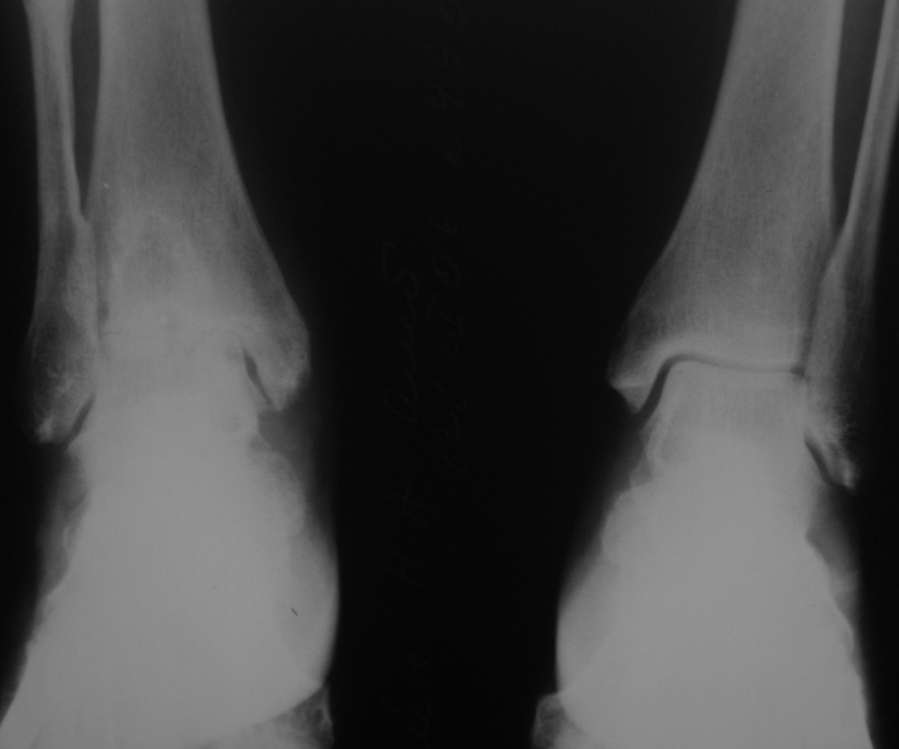

Уважаемые коллеги, разъясните ситуацию.Пациентка, 45лет. 9 месяцев назад произведен синтездвухлодыжечного перелома правой голени.

Конструкции на данный момент удалены. Объем движений на фото. Сейчас беспокоят скованость в области сустава, боли к концу рабочего дня - классическая клиника артроза.Пропила 4 курса найз. Откуда артроз такой выраженности (на рентгенограмме)? Поможет ли консервативное лечение и какое поможет наверняка?

Интересно бы посмотреть операционные снимки и знать сроки иммобилизации, операции по постановке и удалению конструкции и был ли винт в синдесмозе? и когда он удален? когда больная начала давать нагрузку и в боковой проэкции это недостатки обработки рентгенограмм или такой остеопароз.

Артроз, во-первых, вследствие неконгруентности суставных поверхностей - имеется укорочение малоберцовой кости; во-вторых имеется синостозирование берцовых костей (вместо тугоэластисчного синдесмоза).

>Артроз, во-первых, вследствие неконгруентности суставных поверхностей - имеется укорочение малоберцовой

Но укорочение - 3мм, и потом суставная поверхность наружной лодыжки не несет осевой нагрузки

>во-вторых имеется синостозирование берцовых костей (вместо тугоэластисчного синдесмоза).

Даже если это были оригинальные имлантаты "Synthes", то к "АО" этот остеосинтез не имеет ни какого отношения. Потому, что вся философия АО в отношении переломов лодыжек основана на том, что наружная лодыжка это нагружаемая часть сустава, на которую приходится примерно 1\6 веса тела. Восстановление длины м\б кости является приоритетным, и наружную лодыжку называют ключом г\ст сустава.

"Стягивающий винт на синдесмоз" противоречит АО, т.к. этот винт должен быть позиционным и не должен создавать компрессиию на уровне сочленения берцовых костей и между наружной лодыжкой и таранной костью. Стягивающий винт - основная причина синостоза на месте синдесмоза.

этих-то 3 мм и достаточно для формирования артроза. Наружная лодыжка - ключ к голеностопному суставу!